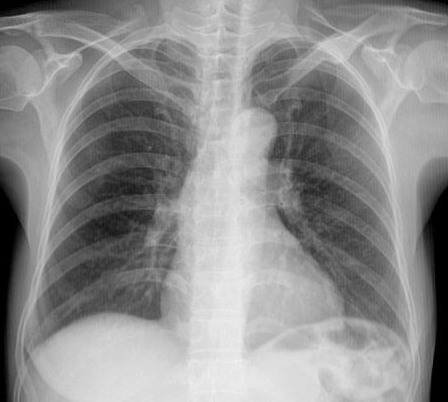

病例1:胸部摄片未见明显异常

病例1:胸部摄片未见明显异常,但CT扫描发现肺上叶磨玻璃密度结节,

术后病理检查:微浸润腺癌